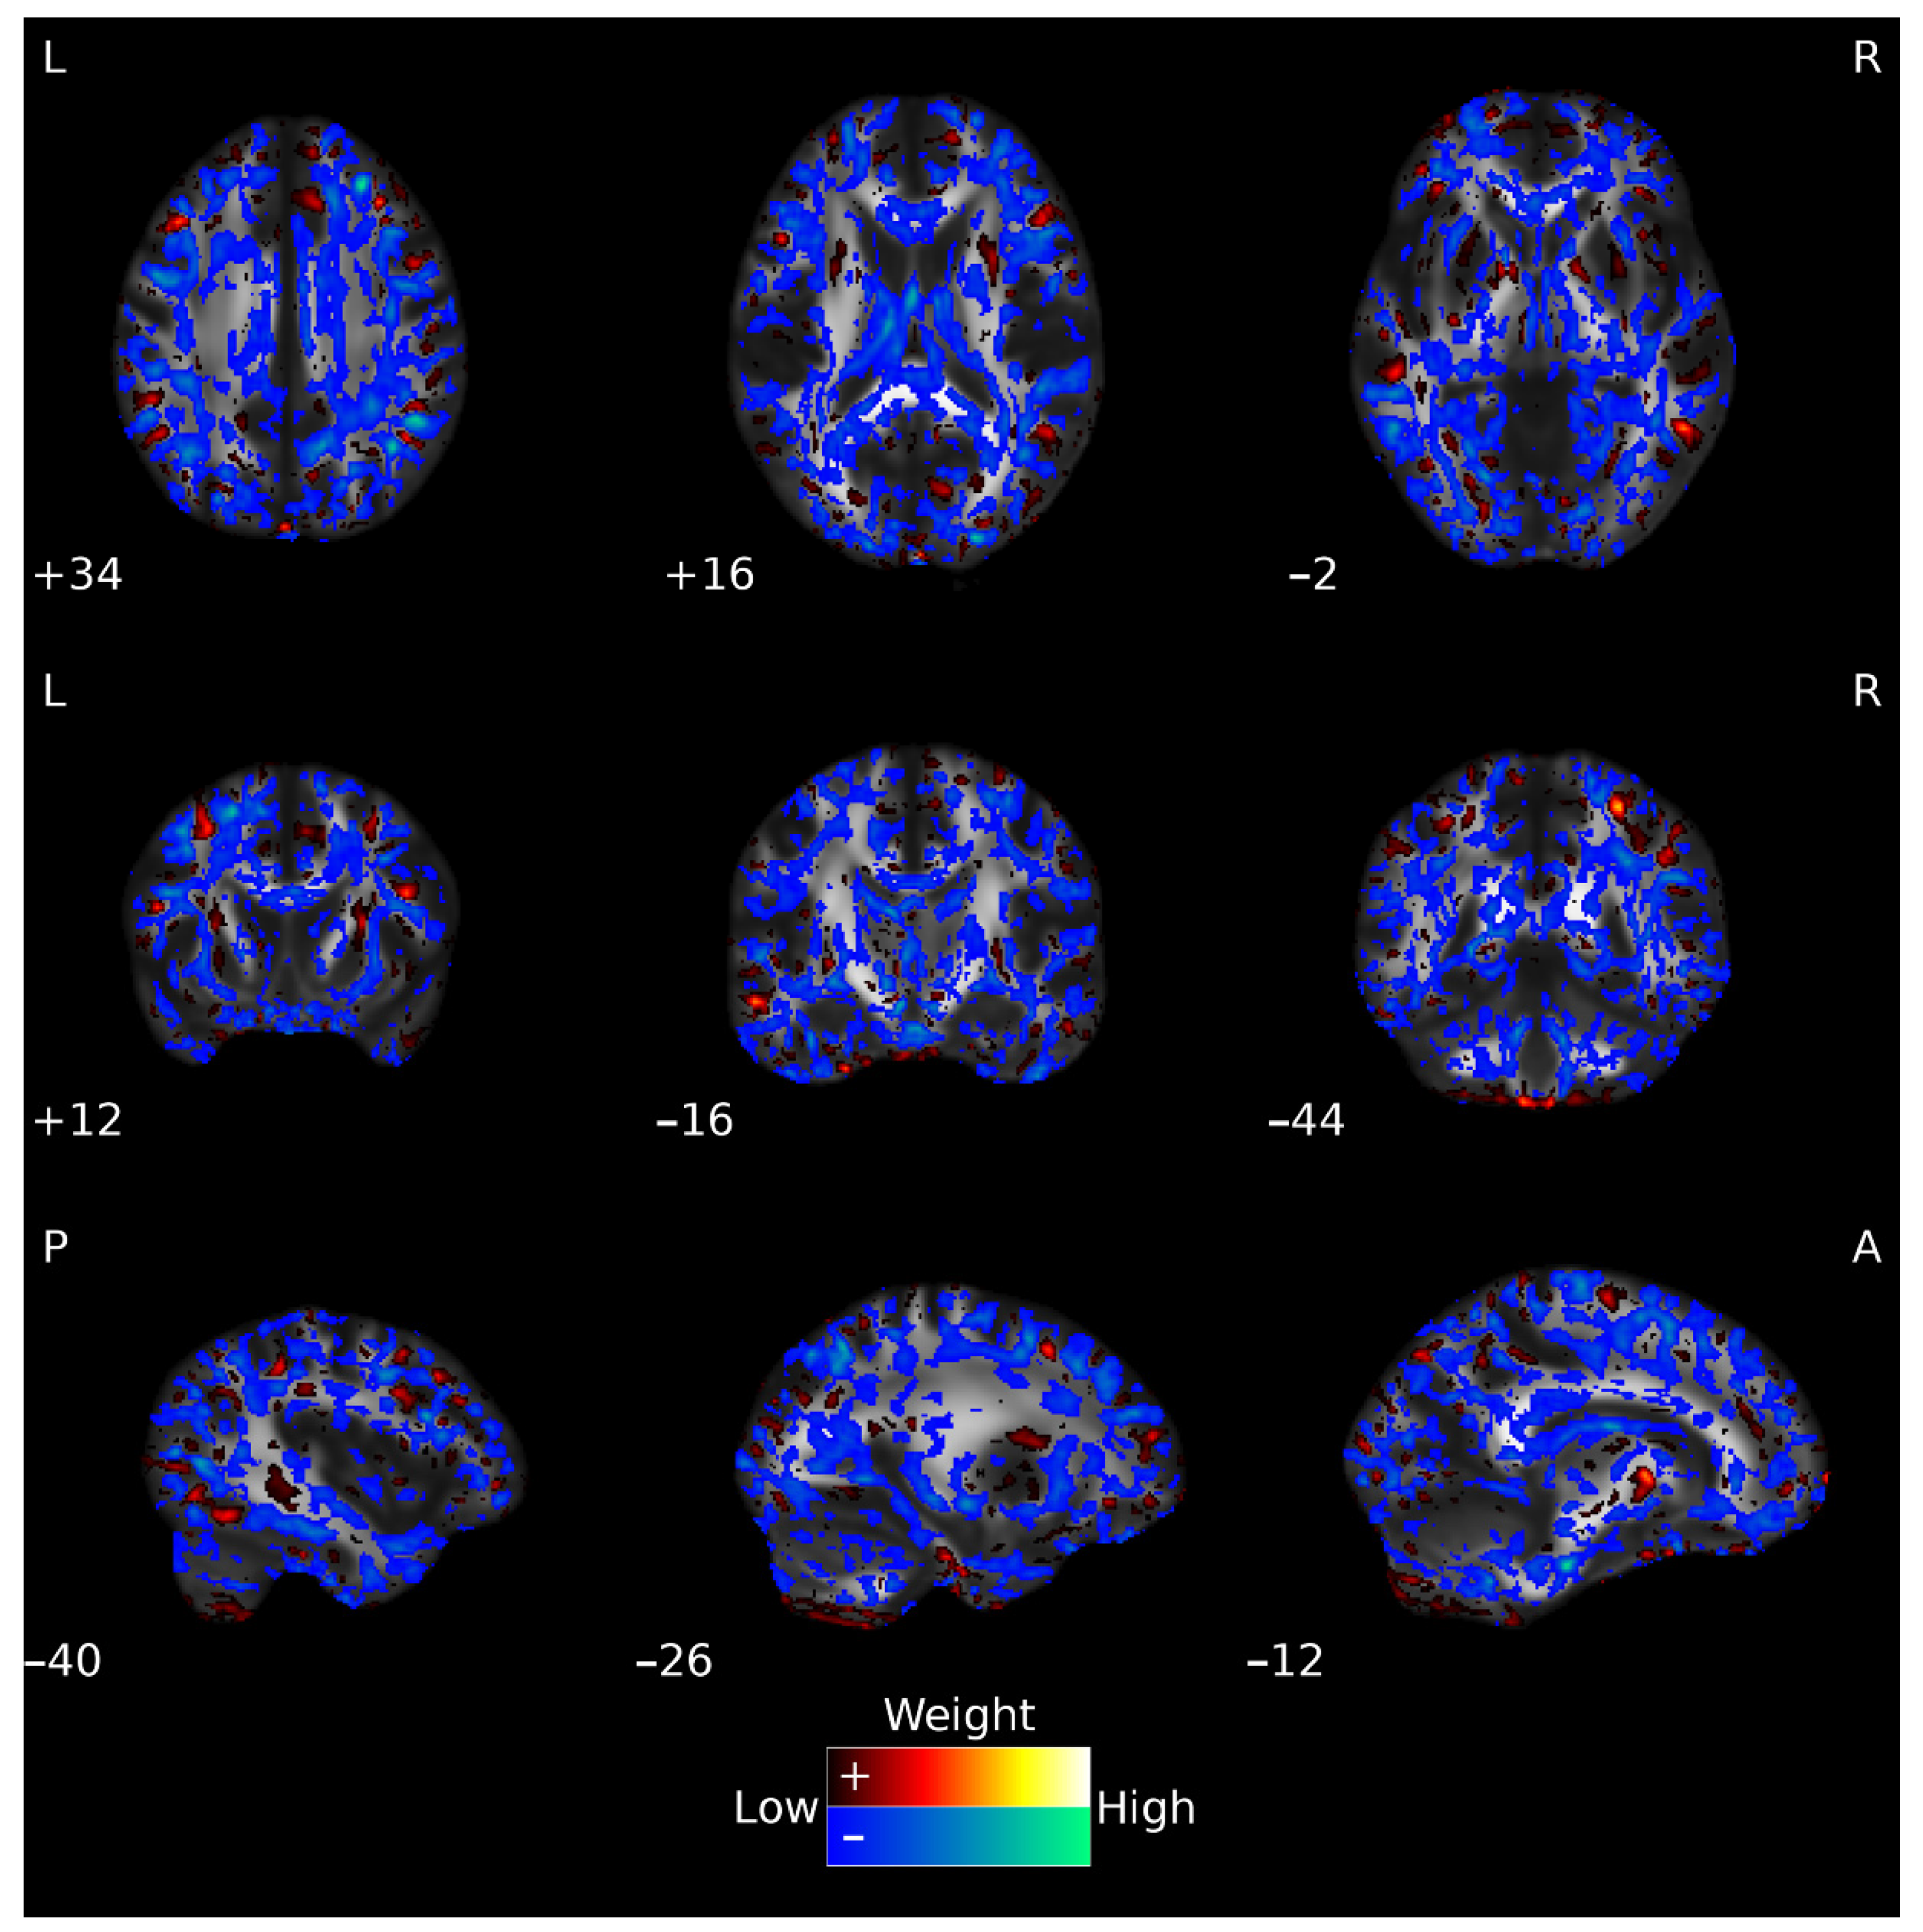

The inspection of the whole-brain (FA) weighting map for the Early-HD vs. Pre-HD classification (see Figure 3) revealed significant contributions from FA values within the distributed regions, including angular, middle frontal, middle temporal, and parietal underlying areas, and, if considering the John Hopkins University white-matter tractography atlas (JHU-atlas), voxels with significant contributing weights were located in the cerebellar peduncle, fornix, cerebral peduncle, and external capsule, between others. Similar contributing patterns were observed for the whole-brain (FA) weight map from the Early-HD vs. HC classification (see Supplementary Materials, Figure S2). When considering weight map of the Relief-F 10,000 features classification model, significant contributions spanned from striatal structures, thalamus, or cerebellum, besides the middle and superior frontal and temporal regions, and when considering the JHU-atlas, significant contributions included features from the corpus callosum, cerebellar peduncle, and external capsule, among others.

Figure 3.

Voxels’ weights for the Early-HD vs. Pre-HD classification using whole-brain FA features. The hot (red-yellow) and cold (blue-green) color maps show the positive and negative weights, respectively. For visualization purposes, weight values at the lowest 10% range (closer to zero, positive, and negative) are not displayed. The ‘Low’ (closer to zero) and ‘High’ (further away from zero) descriptions refer to absolute weight values. The weight values are overlaid on a standard FSL target FA image, FMRIB58_FA. L: left; R: right; P: posterior; A: anterior.